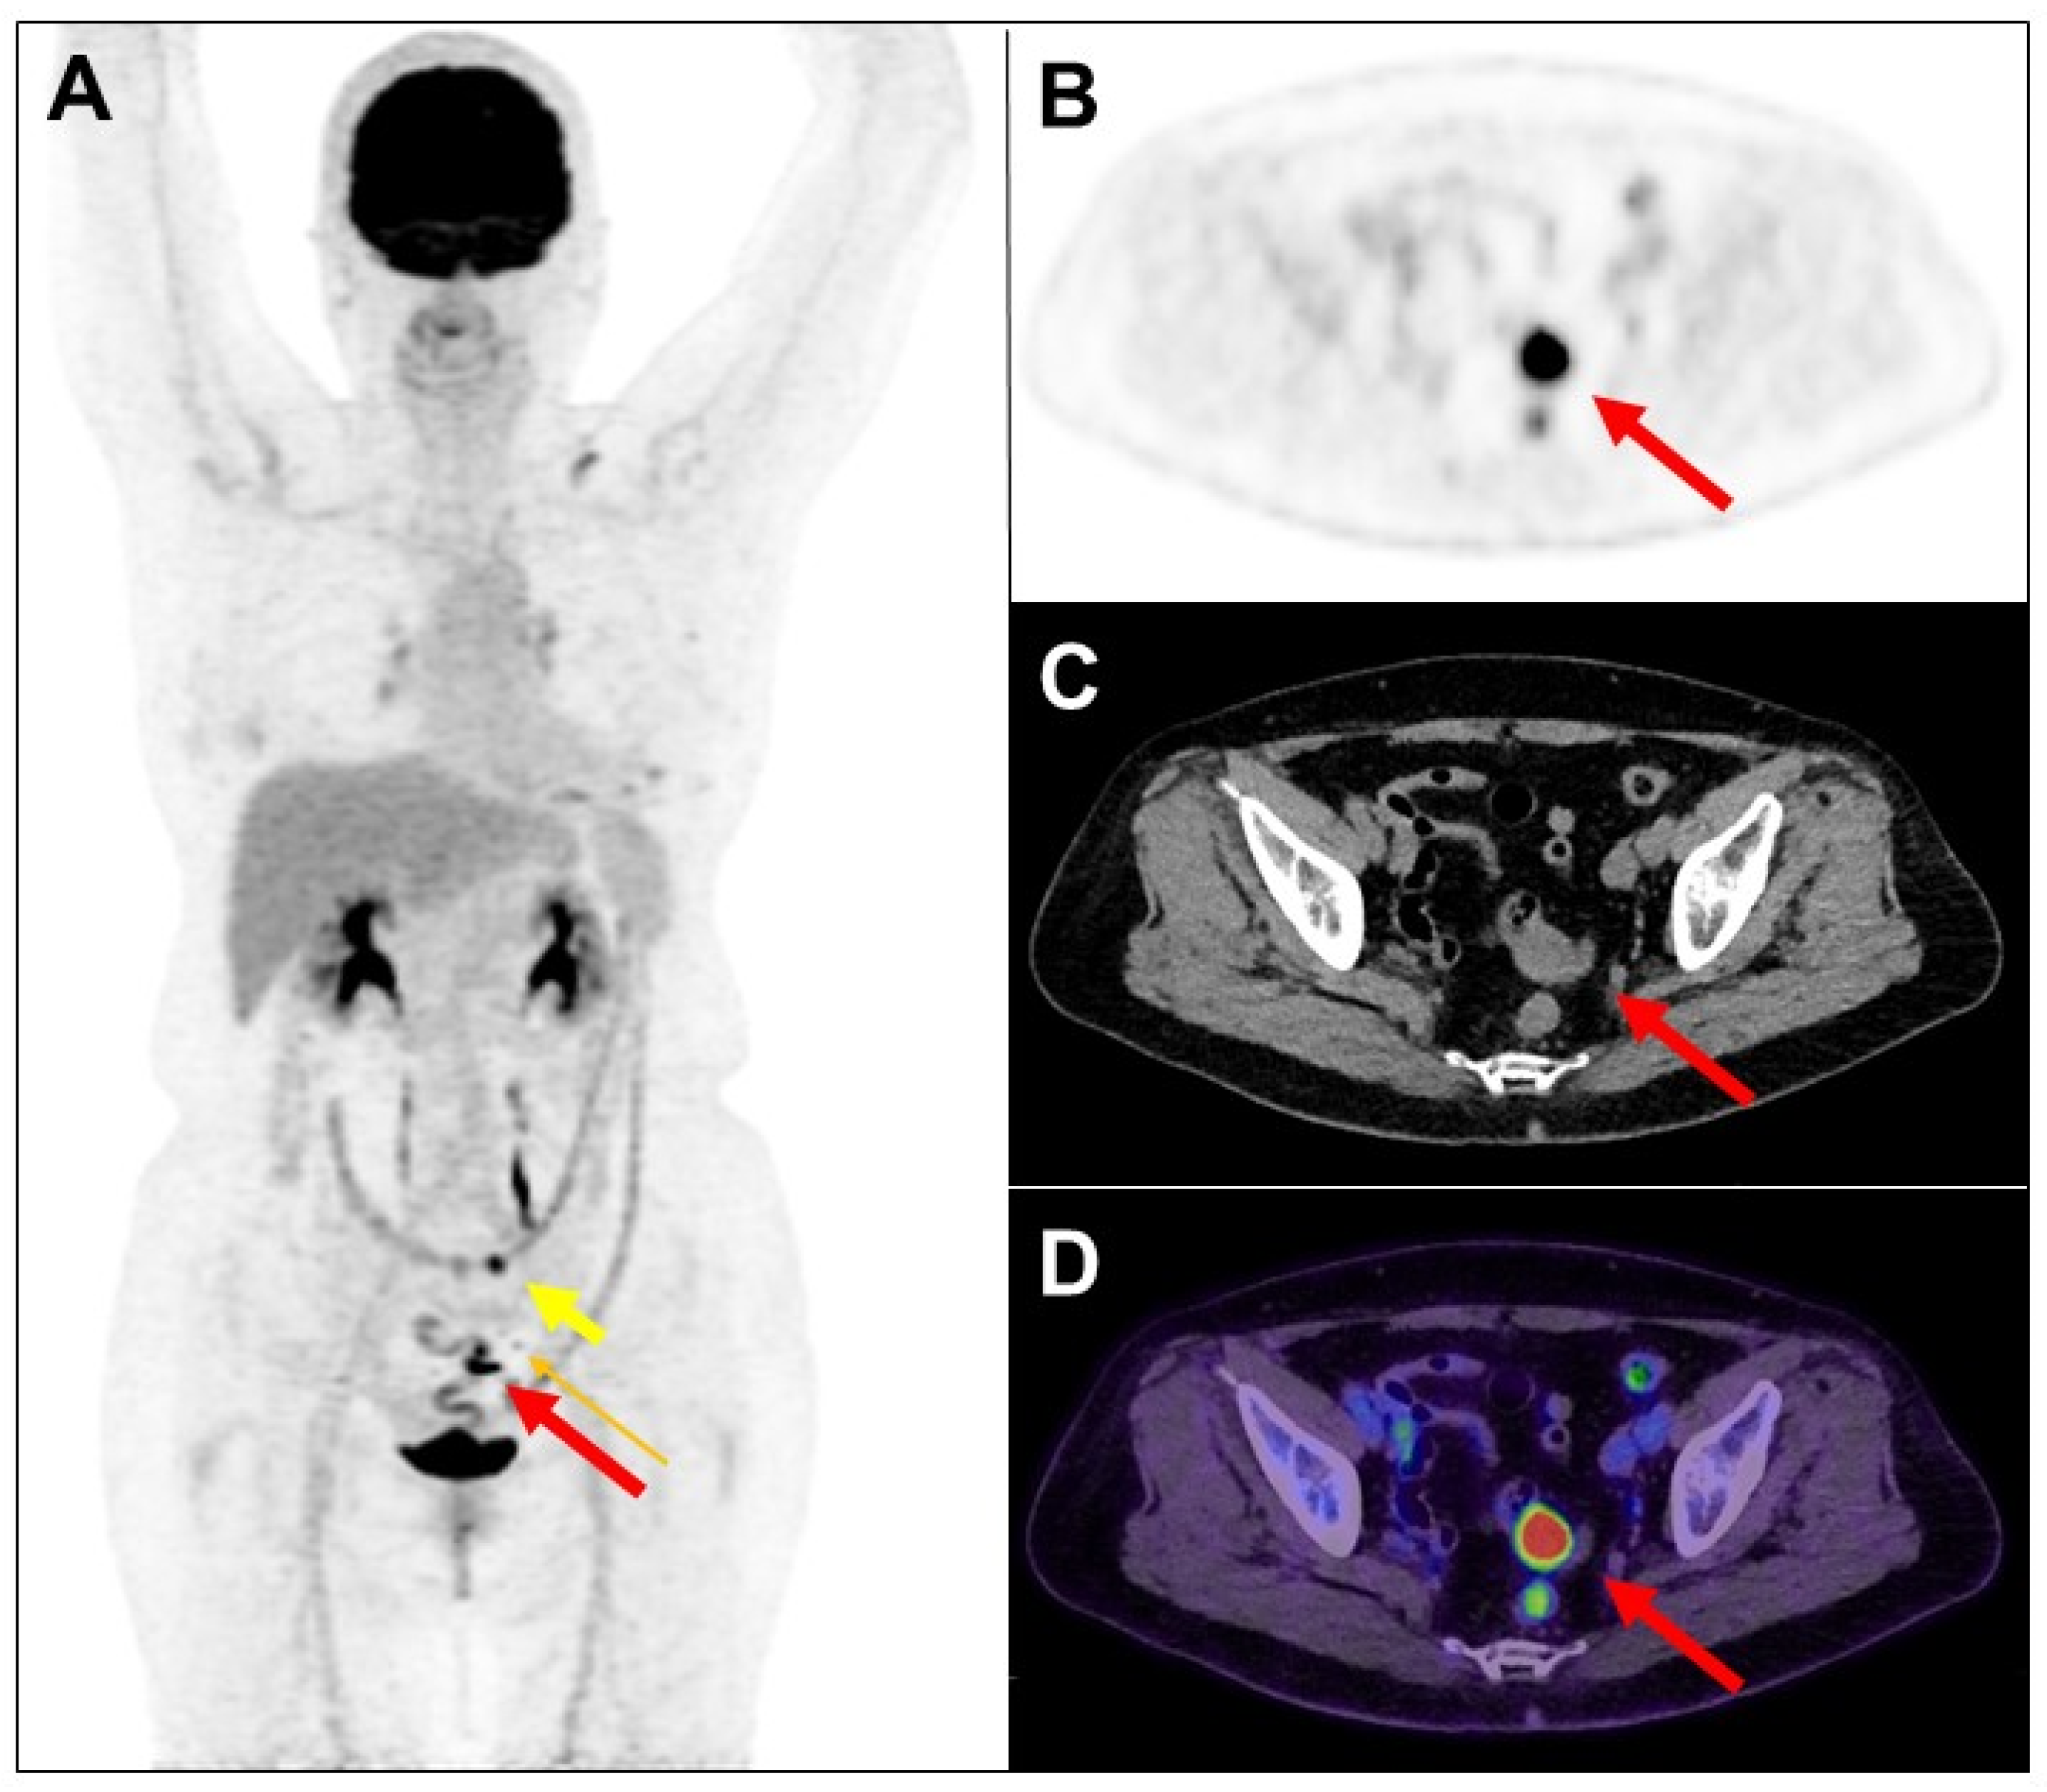

The use of a laxative-augmented contrast medium before a delayed FDG PET/CT scan leads to a reduction in the number of false-positive findings and increases the accuracy in the detection of colorectal cancer [1,2]. Maximum-intensity projection (A), transaxial PET, CT, and fused PET/CT images of delayed FDG PET/CT scan after per-rectal administration of laxative-augmented contrast medium revealed a filling defect with persistent intense FDG uptake in the sigmoid colon (1.8 × 1.8 × 0.6 cm; (A,F,G,H,J,L); long thick arrow), suggesting a hypermetabolic space-occupying lesion in bowel lumen. Further colonoscopy ((I), long thick arrow: red color) revealed a tumor in the sigmoid colon, which was proved to be adenocarcinoma. In addition, hypermetabolic nodule with filling defect in the transverse colon (1 × 0.8 × 0.5 cm; (A–D); short thick arrow) and rectum (1.3 × 0.8 × 0.6 cm; (A,F,G,H); short thin arrow: green color), colonoscopy, and histopathology revealed tubular adenoma and tubulovillous adenoma ((E), short thick arrow: yellow color; (M), short thin arrow: green color), respectively. Another focal mild hypermetabolic nodule in the descending colon (1 × 0.8 × 0.4 cm; (A,N,O,P); arrowhead: blue color) was also noted. The colonoscopy ((Q), arrowhead: blue color) and histopathology revealed tubulovillous adenoma. Later, the patient received laparoscopic anterior resection, and histopathology revealed moderately differentiated adenocarcinoma (2.0 × 2.0 × 0.6 cm) in stage pT1N1b. Lymph nodes had one metastasis to the pericolic ((A,J,K,L); long thin arrow: orange color) and inferior mesentery artery regions, respectively. Colorectal cancer is the third-leading cause of cancer death in the world [3]. Colorectal cancer usually begins with the most common form: an adenoma that originated from granular cells [4]. The proportion of colon adenoma to adenocarcinoma detected by FDG PET/CT scan is about 73% to 27% [5]. FDG PET is a sensitive imaging method for the detection of colorectal malignancy. However, benign, infectious, inflammatory, and granulomatous processes may also cause an increase in FDG uptake. Delayed FDG PET/CT performed after administration of a laxative-augmented contrast medium might be useful for identifying patients needing additional diagnostic procedures or avoiding unnecessary colonoscopic evaluation. The protocol consists of an initial phosphosoda enema (Fleet; C.B. Fleet, Lynchburg, VA, USA). Following the evacuation, 500 mL of diluted 3% contrast medium (Conray, iothalamate meglumine USP 60%; Mallinckrodt Inc., St Louis, MO, USA) is instilled into the anus. In this case, we used per-rectal administration of laxative-augmented contrast medium, and the detection of adenomas number was increased. An FDG-avid filling defect, suggesting hypermetabolic nodule with the space-occupying lesion, was discovered in an FDG PET/CT scan.